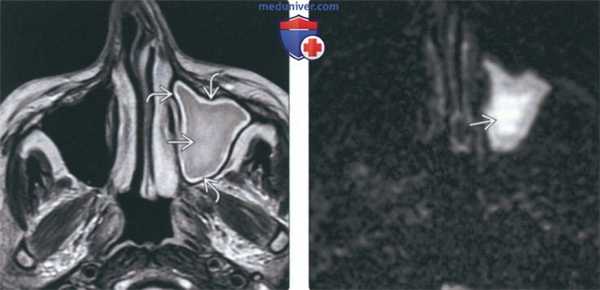

(Слева) Аксиальная ADC-карта у этого же пациента подтверждает рестрикцию диффузии как причину гиперинтенсивного сигнала при MPT DWI. В содержимом левой верхнечелюстной пазухи определяется снижение интенсивности сигнала, в слизистой оболочке на периферии интенсивность сигнала повышена.

(Справа) При аксиальной КТ в костном окне у пациента с хроническим фронтитом определяется утолщение слизистой оболочки, выраженное утолщение стенок пазух, особенно слева. Изменения слева имитируют фиброзную дисплазию.

(Слева) На аксиальной ADC-карте у этого же пациента определяется ограничение диффузии (как причина сигнала высокой интенсивности на DWI). Интенсивность сигнала снижена в секрете и повышена в слизистой оболочке на периферии.

(Справа) На аксиальной КТ в костном окне у пациента с хроническим фронтитом определяется утолщение слизистой оболочки обеих лобных пазух. Стенки пазух, особенно левой, в значительной аепени утолщены. Слева изменения напоминают фиброзную дисплазию, но без вздутия.